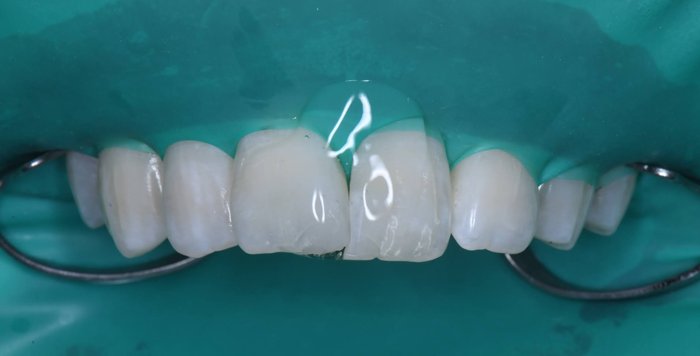

症例2:欠けた歯を治したい

治療前

治療後

治療中の様子

修復した最後に、酸素で阻害された表面(Oxygen Inhibitation Layer)を最終重合しています。

| 主訴 | 欠けた歯を治したい |

|---|---|

| 治療期間 | 1日 |

| 治療費 | ¥22,000 |

| 治療内容 | コンポジットレジンにて修復しました。切端の透明感や亀裂(クラック)を隣の歯と同じように再現できました。患者様には大変満足していただけました。 |

| 治療のリスク | 欠けたり、経年的な変色の可能性があります。 |